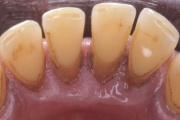

Krooniline parodontiit

Krooniline parodontiit on mikroobide poolt põhjustatud hammaste tugikudede põletik, mille tulemusena tekib progresseeruv alveolaarluu (nähtav röntgenograamil) ja periodontaalligamendi destruktsioon, igemetaskute moodustumine, igeme retsessioon või mõlemad kahjustused kombineeritult. Loe edasi »

- igemepiir on taandunud (3)

- luu destruktsioon (5)

- horisontaalne luukadu (3)

- hamba kinnitussidemete kadu (3)

- igemepealne hambakivi (5)

- igemealune hambakivi (4)